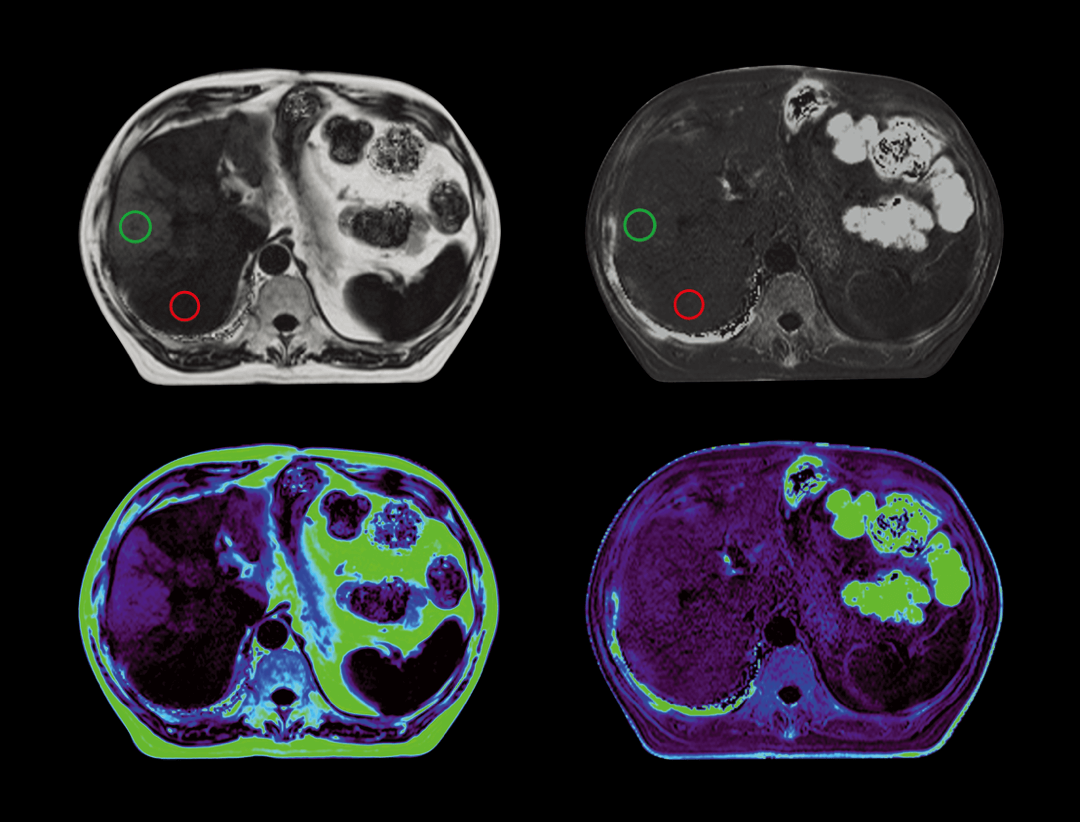

光梭®2.0成像应用于磁共振腹部动态增强扫描,可实现16倍采集加速,清晰捕捉组织信号连续动态变化,精准捕获腹部动态影像的每一瞬间,实时、全方位锁定病灶。

脂肪定量

无创检测组织内脂肪含量及铁沉积,一次扫描输出多参数图像,可以同时提供精确脂肪含量值以及铁沉积程度。